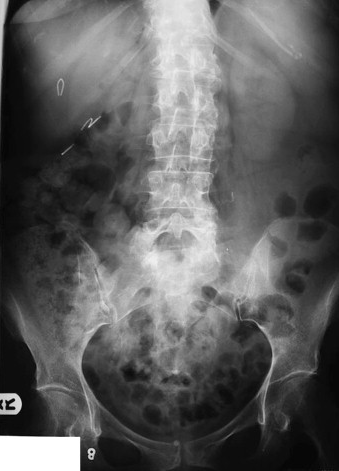

What is this abdominal x-ray showing?

Cannot see psoas so AAA